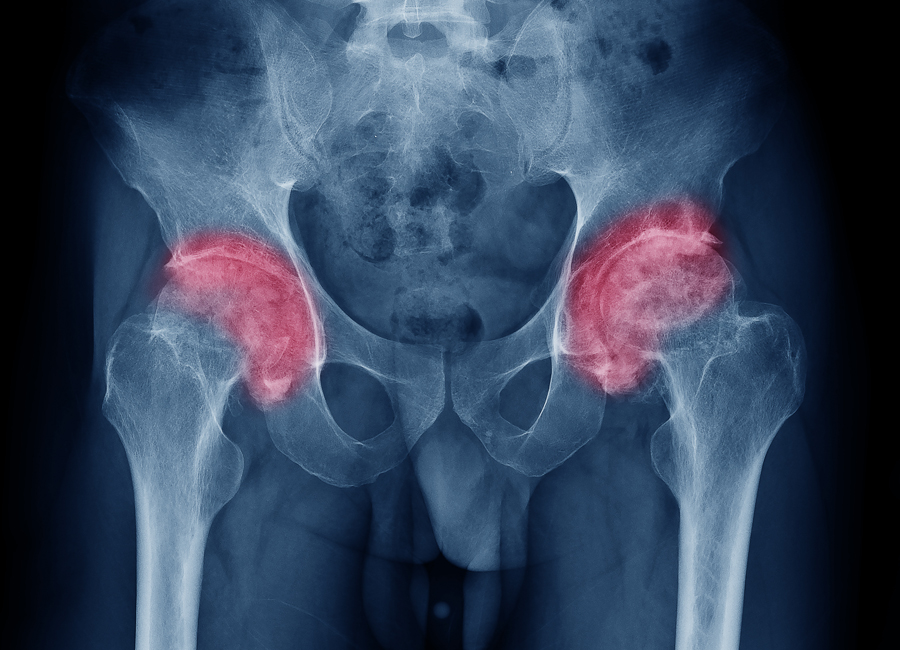

У спортсменов сверхнагрузка, которая падает на суставы, изнашивает их намного раньше срока, предназначенного им природой. Стирание происходит быстрее. Я 20 лет профессионально занималась спортом. Никто мне не рассказывал, чего ожидать в будущем и как аукнутся все мои достижения. Поэтому я усердно тренировалась и защищала честь страны, выступая на международных соревнованиях. В итоге — операция по смене тазобедренного сустава.